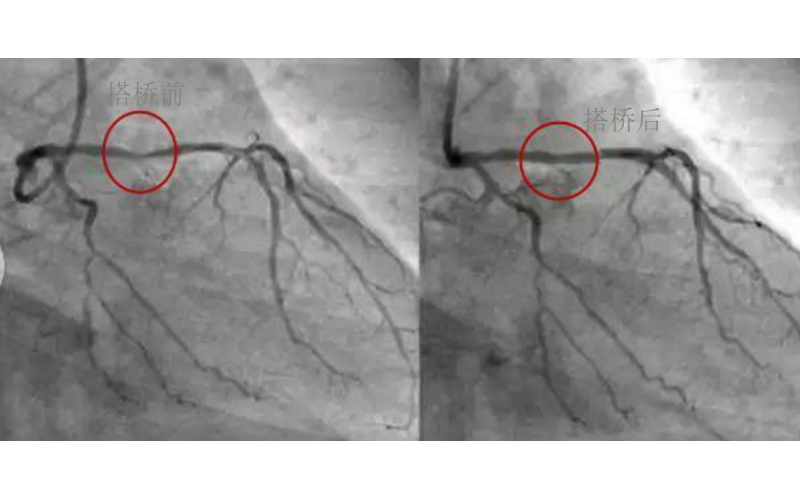

深圳市模具厂对心脏支架的关注,国产化的道路有多长?